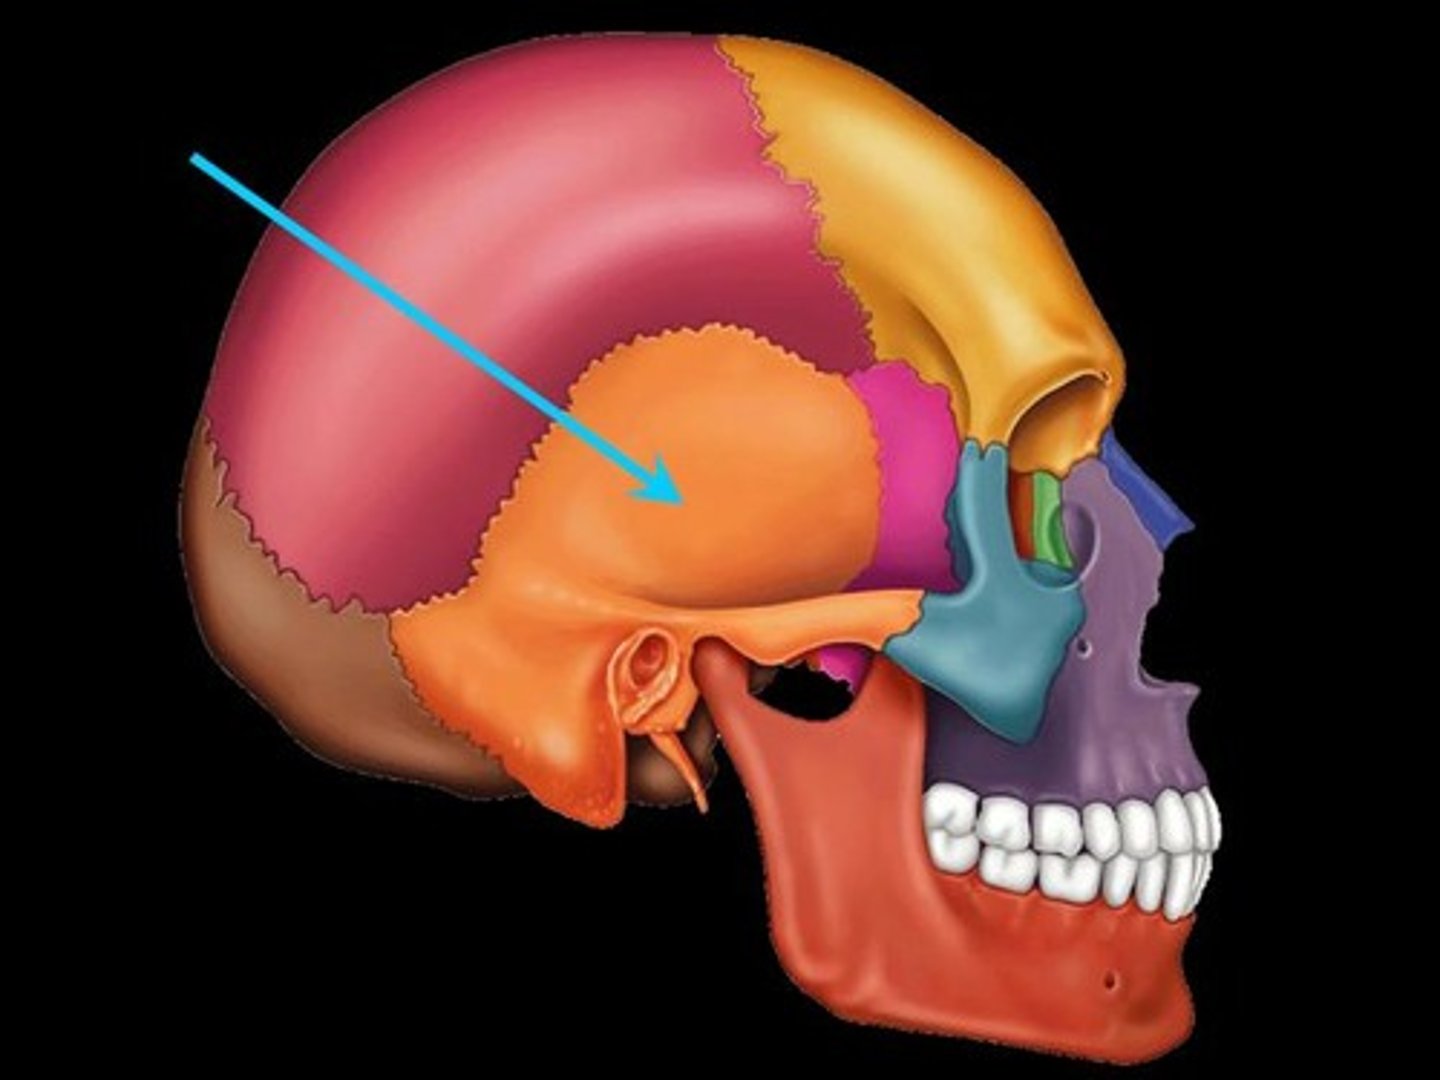

Temporal Bone

bone that forms parts of the side of the skull and floor of the cranial activity. There is a right and left temporal bone.